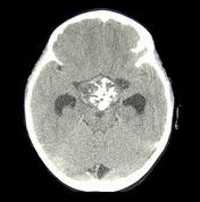

Длительное течение заболевания сказывается на формировании костей. Так, н а поздних стадиях вовремя не диагностированного гиперпаратиреоза наблюдаются:

- разрушение дистальных или концевых фаланг конечностей;

- сужение дистального отдела ключиц;

- очаги разрушения костей черепа;

- бурые опухоли длинных костей.